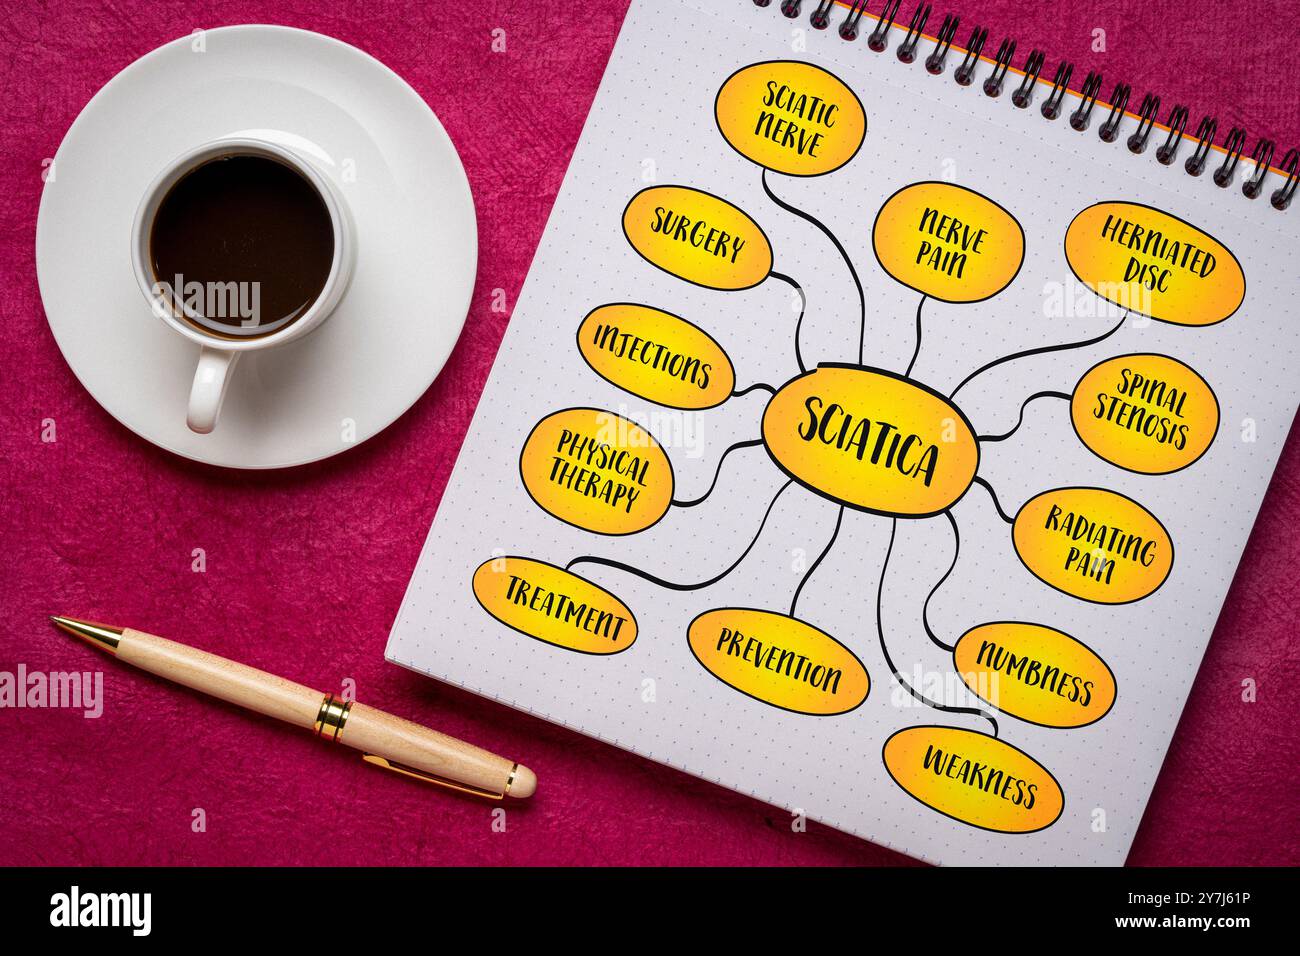

Sciatique se réfère à la douleur qui rayonne le long du chemin du nerf sciatique, le plus grand nerf dans le corps, infographie de carte mentale. Banque D'Imageshttps://www.alamyimages.fr/image-license-details/?v=1https://www.alamyimages.fr/sciatique-se-refere-a-la-douleur-qui-rayonne-le-long-du-chemin-du-nerf-sciatique-le-plus-grand-nerf-dans-le-corps-infographie-de-carte-mentale-image624275730.html

Sciatique se réfère à la douleur qui rayonne le long du chemin du nerf sciatique, le plus grand nerf dans le corps, infographie de carte mentale. Banque D'Imageshttps://www.alamyimages.fr/image-license-details/?v=1https://www.alamyimages.fr/sciatique-se-refere-a-la-douleur-qui-rayonne-le-long-du-chemin-du-nerf-sciatique-le-plus-grand-nerf-dans-le-corps-infographie-de-carte-mentale-image624275730.htmlRF2Y7J61P–Sciatique se réfère à la douleur qui rayonne le long du chemin du nerf sciatique, le plus grand nerf dans le corps, infographie de carte mentale.